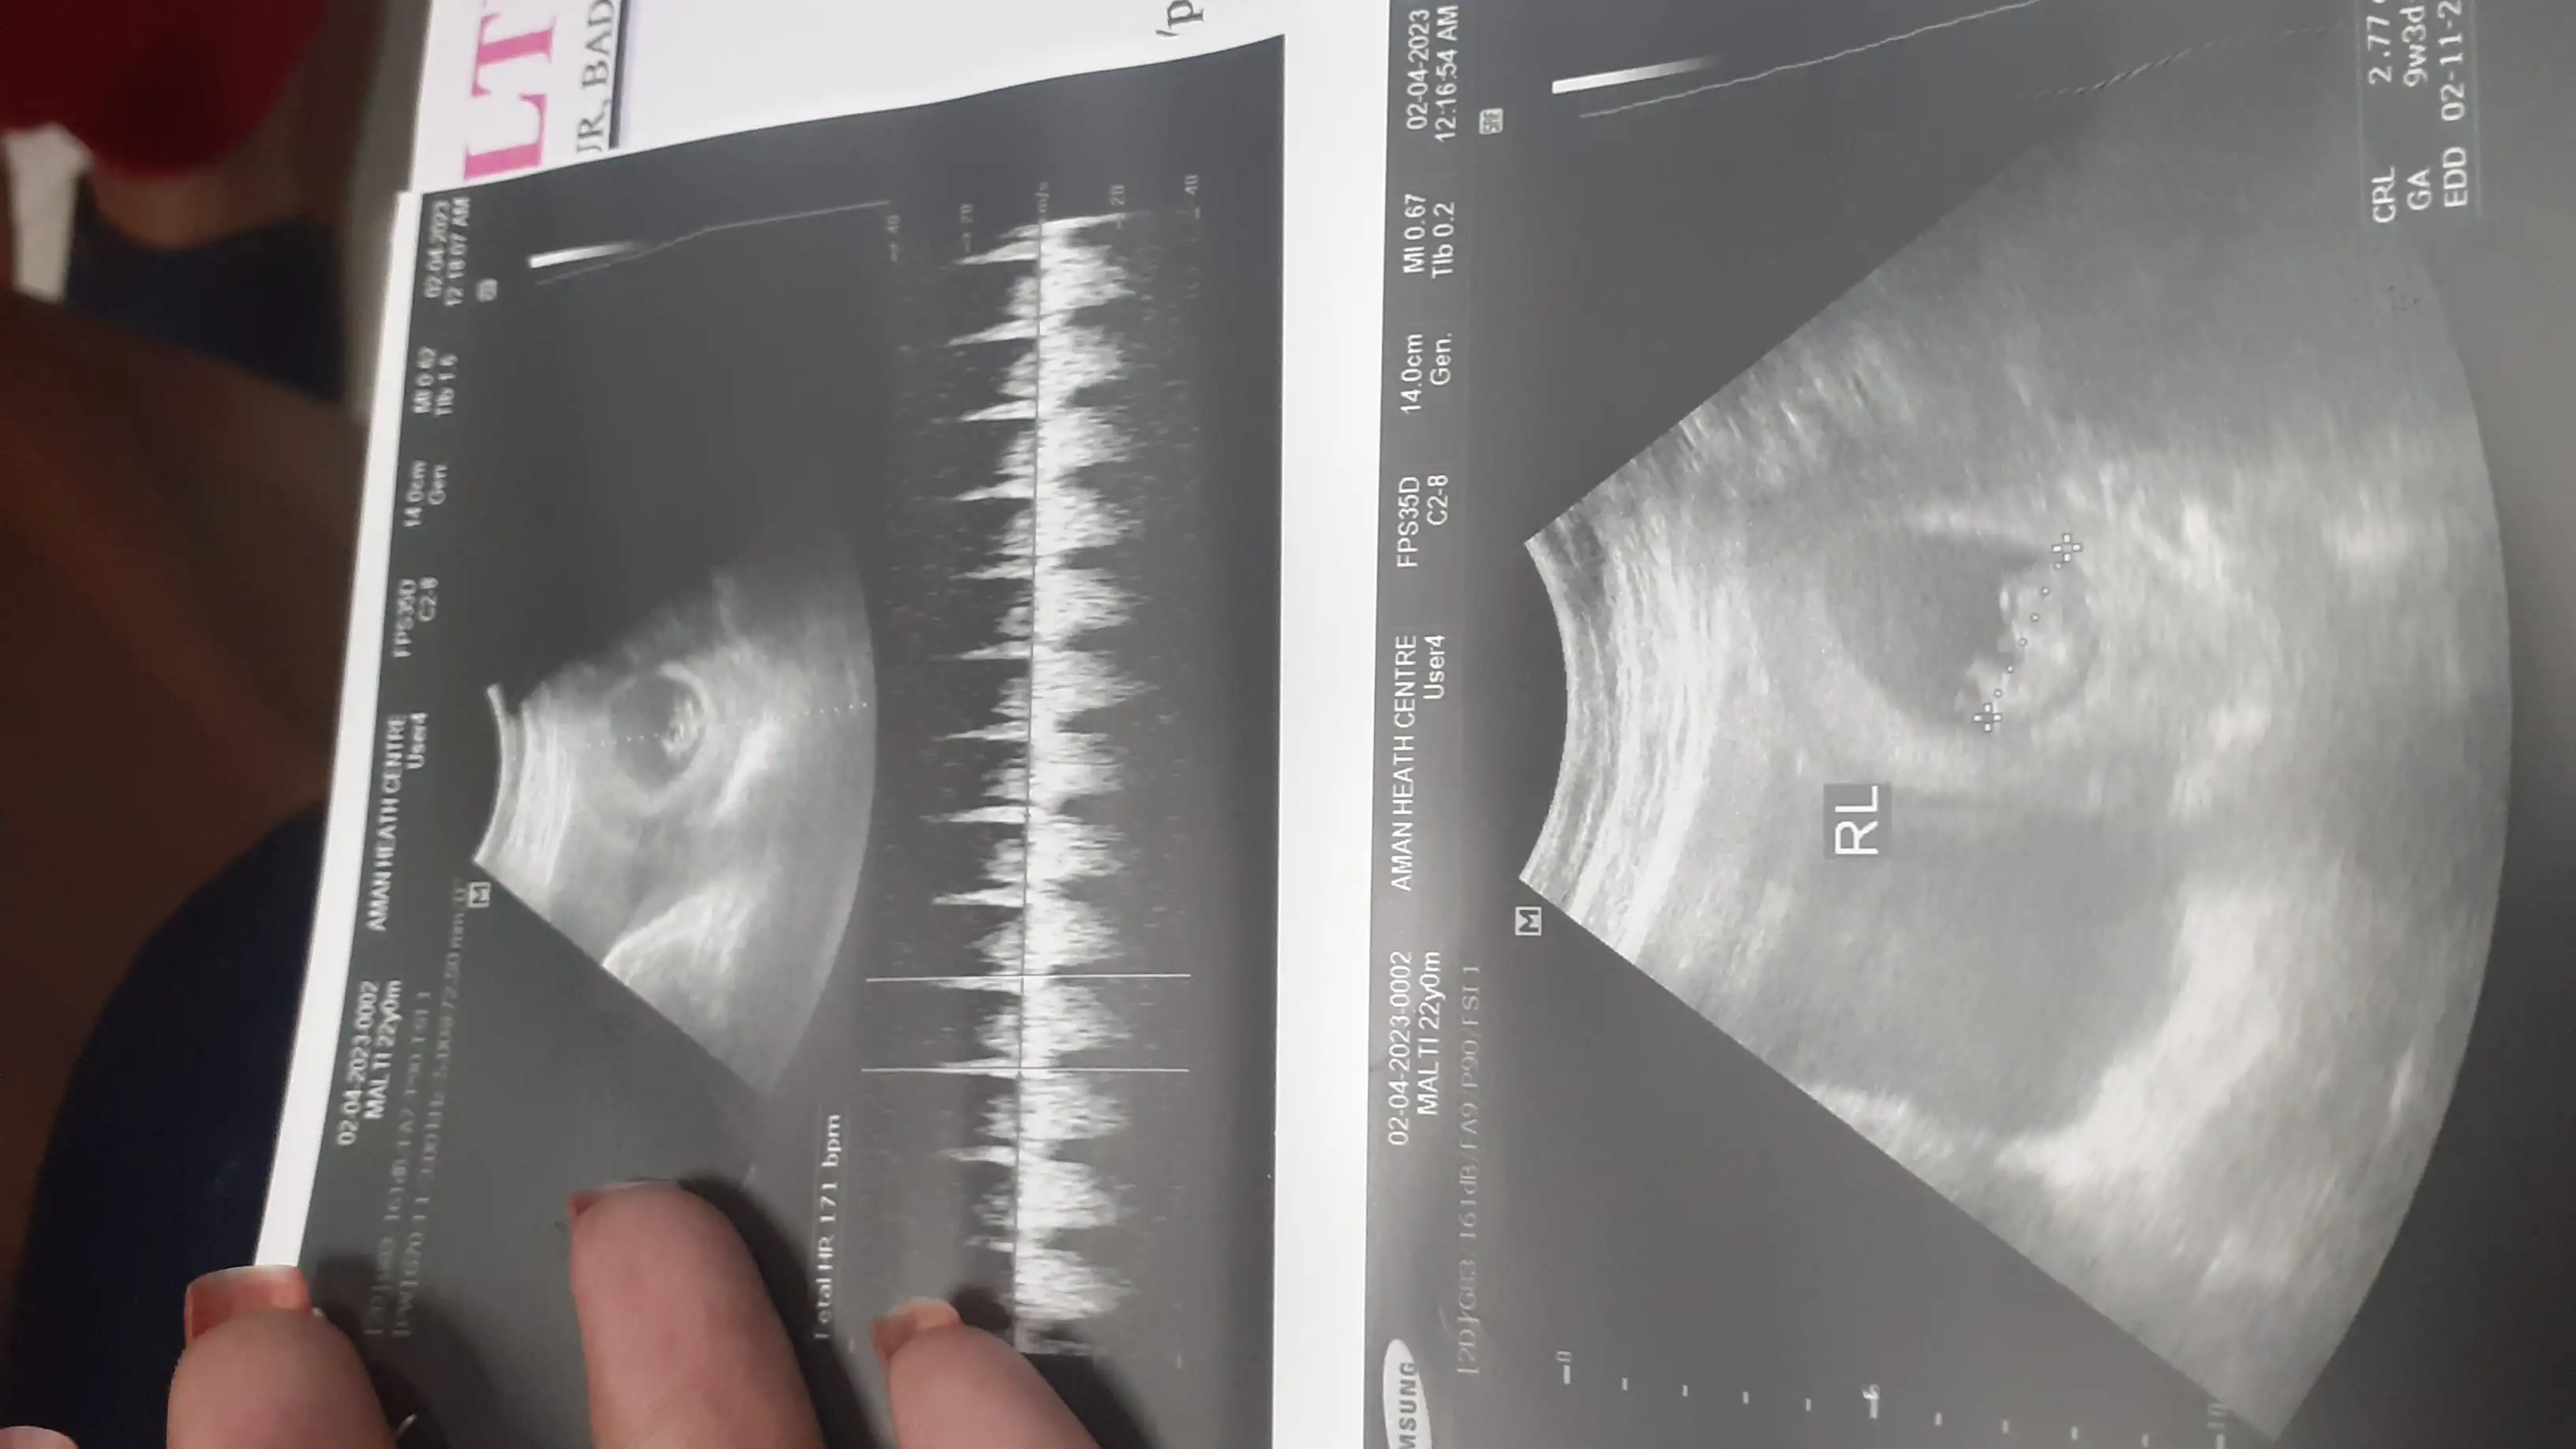

Q: Mera ultrasound aaj hua hai our mere baby ka hurdbit bhi aa gaii hai

• Hello sisters please meri ultrasound report dekhkar bataiye ki sab Kuch hai .... our meri pregnancy ko kitne din ho gay me bahut confused Hu ....mere hisaab se 7th month abhi start hua hai doctor ne Bola hai ki 7 month complete hone wala hai ..... please help me